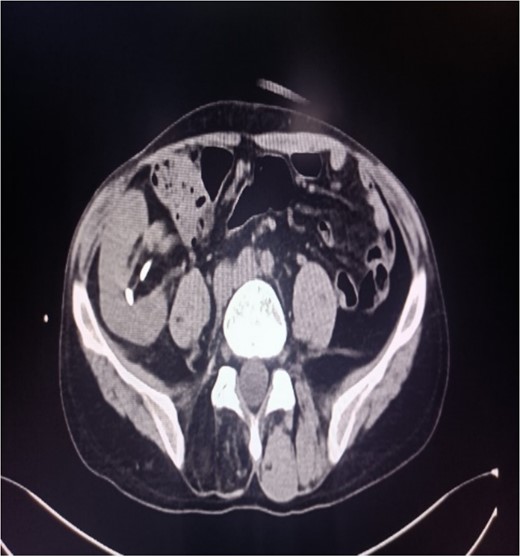

Abdominal CT showing multiple punctate stones in the right renal area in situ.

A 39-year-old man with kidney stones after kidney transplantation was admitted to our hospital on 29 November 2023. Eight years ago, he underwent a kidney transplant from a donor. Neither the donor nor the recipient had a history of kidney stones. The transplanted kidney was positioned in the right iliac fossa, and the patient had a successful postoperative recovery. However, a recent routine abdominal computed tomography (CT) scan revealed multiple stones in the transplanted kidney and bilateral in situ kidney atrophy. The stone was located in the lower calyx of the transplanted kidneys. Hydronephrosis was also observed. Kidney, ureter, and bladder radiographs showed multiple high-density speckles in the right kidney, the largest of which was ~0.5 cm in diameter. Physical examination (blood pressure, 147/91 mmHg; serum creatinine, 72.7 μmol/L; urea nitrogen, 5.1 mmol/L) revealed normal liver function, coagulation, and electrolytes. We suspected that these kidney stones were sizable and necessitated surgical intervention. Upon admission, pertinent examinations were conducted, and preoperative preparations were completed.